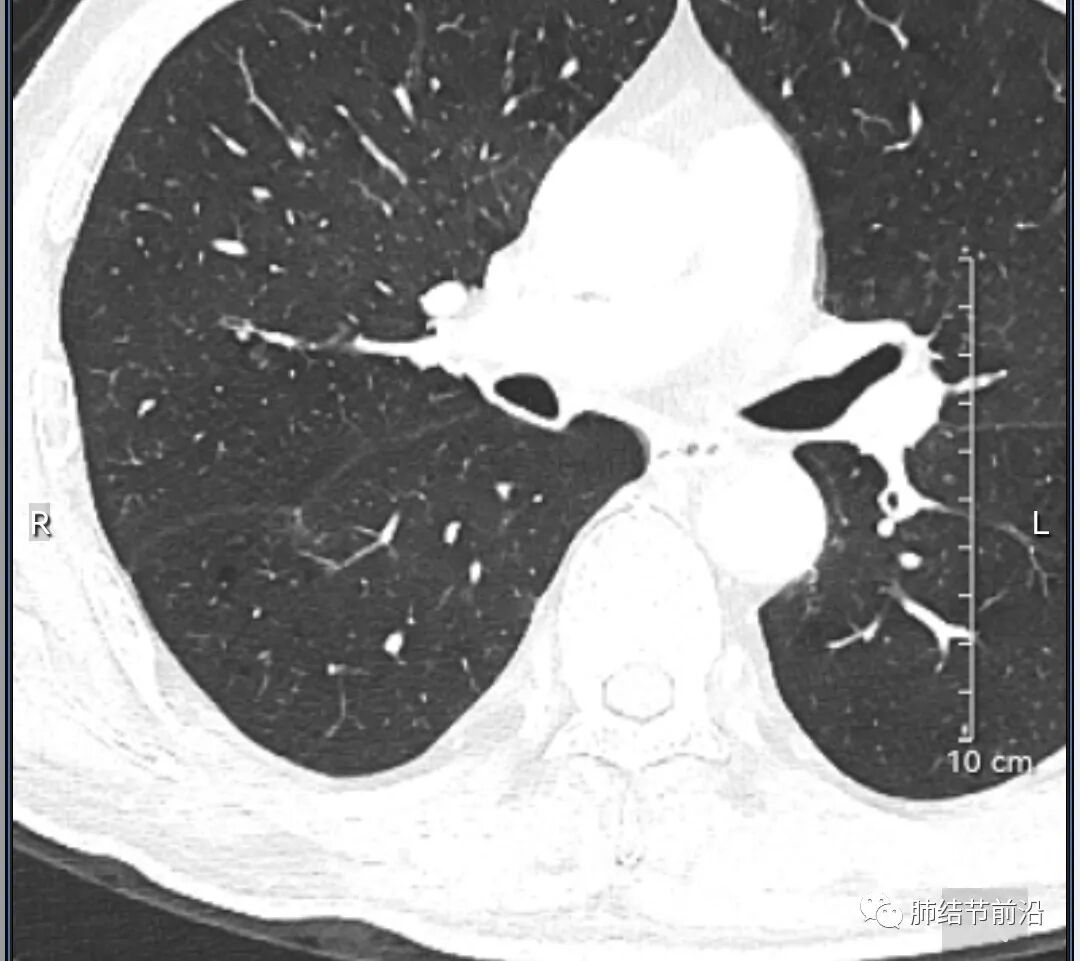

男性,67岁,重度吸烟史。CT发现右下肺囊腔。来看一下这个CT的特点:

该囊腔形态非常有特点,和常见的圆形肺大泡有很大的区别。

1.囊腔中央实性成分,周围有磨玻璃影。

2.囊腔中央有血管。

3.囊腔外周有分叶形态。

4.囊腔有胸膜牵拉。

出现这几种形态,CT可以确认恶性的腺癌。这个囊腔形成的机制,为肿瘤实性成分堵塞细支气管形成活瓣,肺泡内压力增高破裂行成,因此肺内血管成分保留。由于肺泡压力增高,而呈分叶状。另外,也有肿瘤的胸膜牵拉这一特点。

囊腔周围磨玻璃+囊腔中央血管为特征性表现。如果持续存在,几乎可以100%确认为早期肺腺癌。